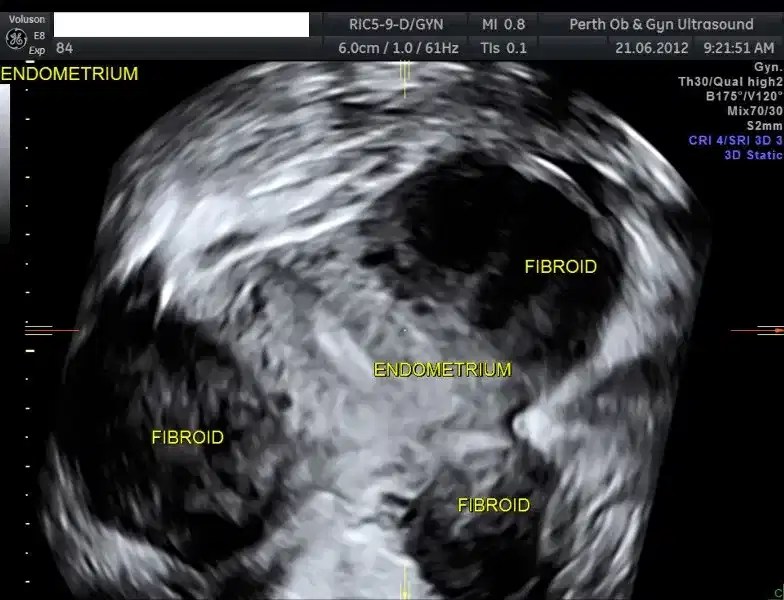

from pogu.com.au

Pelvic Ultrasound POGU

3D Pelvic Ultrasound 3D Pelvic Scan POGU What Is A 3D Pelvic Ultrasound A pelvic ultrasound is an imaging test that uses sound waves to make pictures of what's inside your pelvis. Your pelvis is the part of your. What is a pelvic ultrasound? A pelvic 3d ultrasound includes a routine pelvic ultrasound with additional 3d views. During an exam, a technologist uses a special probe to take many. It provides detailed views. What Is A 3D Pelvic Ultrasound.